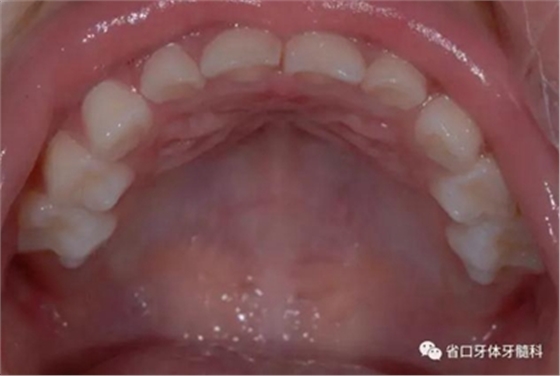

圖7 上頜牙相